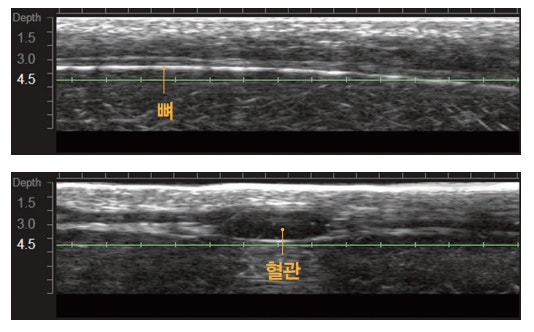

그리고 울쎄라는 슈링크와는 다르게 실시간으로

피부 속을 직접 확인하며 뼈와 혈관을 피해

시술할 수 있다는 점입니다.

직접 볼 수 있다는 것은 집속된 에너지를

뼈나 혈관, 또는 성형이나 필러 시술 등으로 인해

발생한 보형물 또는 삽입물을 피할 수 있다는

것이며, 눈가와 같이 얇은 피부층이나 턱이나

볼과 같이 두꺼운 피부층을 모두 고려하여

타겟팅 할 수 있다는 점입니다.

그리고 피부에 팁이 닿아야만 피부 속을 확인할 수

있는 만큼 피부와 팁의 미접촉 문제로 발생할 수

있는 시술의 부작용(화상 등)을 예방할 수 있습니다.